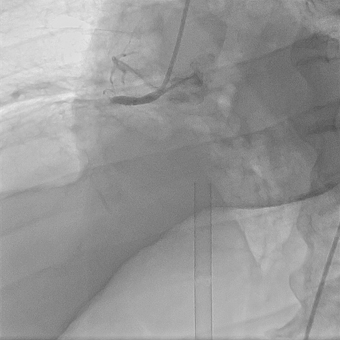

Пациент К., 47 лет, поступил в отделение кардиореанимации с острым инфарктом миокарда. В момент поступления у пациента развилась фибрилляция желудочков с остановкой кровообращения. Начаты реанимационные мероприятия. Многочисленные попытки дефибрилляции, несмотря на непрямой массаж сердца, искусственную вентиляцию легких, вводимые препараты были неэффективны. По кардиомонитору регистрировался идиовентрикулярный ритм с переходом в асистолию — остановка сердца. На фоне проведения непрямого массажа сердца принято решение начать процедуру экстракорпоральной мембранной оксигенации (ЭКМО), чтобы поддержать гемодинамику и сделать возможным перевод пациента в операционную для реваскуляризации миокарда.

В рентгеноперационной после выполнения коронарографии выявлен тромбоз крупной правой коронарной артерии с полным прекращением кровотока. Рентгенэндоваскулярный хирург произвел реканализацию тромбированного участка с аспирационным удалением тромба и стентированием правой коронарной артерии.